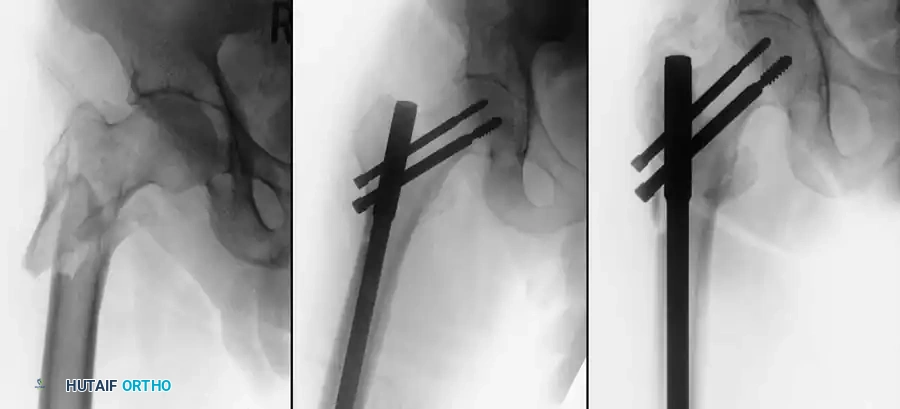

3. Guide Wire Placement

Whether using an SHS or a CMN, accurate placement of the guide wire into the femoral head is the most critical step of the operation.

Insertion of the guide wire. The wire must be positioned centrally in the femoral head on both AP and lateral views.

The Tip-Apex Distance (TAD):

Described by Baumgaertner, the TAD is the sum of the distance from the tip of the lag screw to the apex of the femoral head on both the AP and lateral radiographs. A TAD of less than 25 mm is strongly predictive of successful fixation; a TAD > 25 mm significantly increases the risk of screw cut-out.

5. Intramedullary Nailing (For Unstable Fractures)

If a cephalomedullary nail is chosen, the entry point is established at the tip of the greater trochanter (or slightly medial, depending on the specific implant design).

Insertion of the cephalomedullary nail down the femoral shaft. Care must be taken not to distract the fracture site during insertion.

After the nail is seated, the proximal lag screw(s) are inserted through the nail into the femoral head, adhering to the same TAD principles.

Proximal locking of the cephalomedullary nail. The targeting guide ensures accurate trajectory into the femoral neck.

Finally, distal locking screws are placed to control rotation and maintain length.

Final fluoroscopic evaluation confirming anatomical reduction, optimal implant placement, and restoration of the neck-shaft angle.